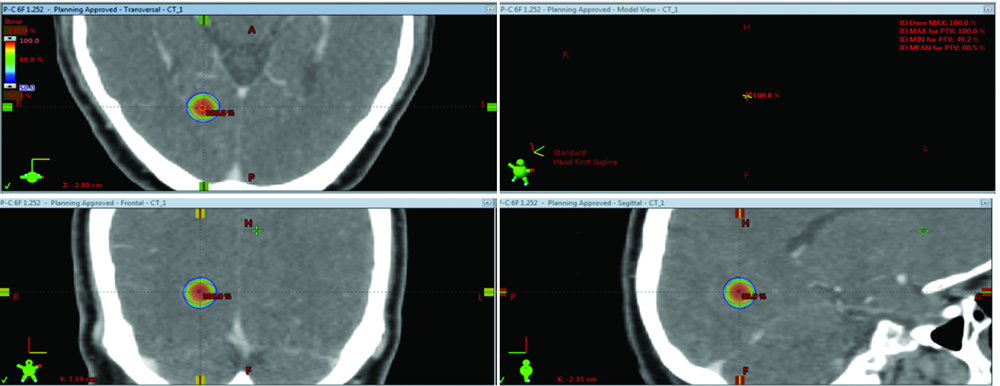

| [2] | 赵永瑞, 高莹, 陈怡东, 徐建堃. 基于直线加速器的分次立体定向放疗对小体积脑转移瘤的有效性及安全性[J]. 国际肿瘤学杂志, 2023, 50(3): 138-143. |